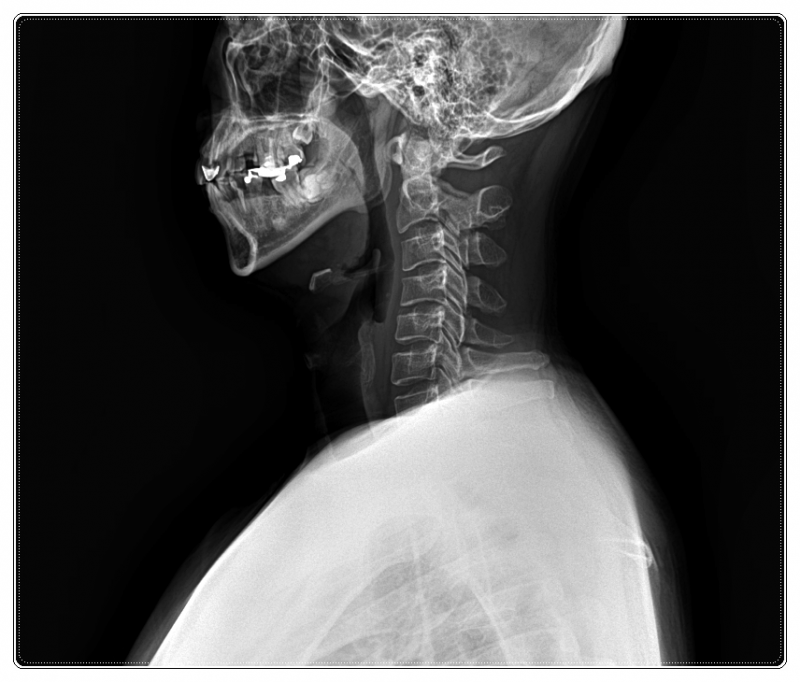

목디스크 수술 후 재활, 왜 다시 불편해질까요

목디스크로 오랜 기간 통증을 겪는 동안, 목 주변 근육과 인대는 굳어 있고 고개를 움직이는 방식 역시 달라져 있는 경우가 많습니다.

• 틀어진 목뼈와 턱관절 위치 점검

이처럼 구조적인 균형이 맞아야 디스크에 가해지는 압력을 줄일 수 있기 때문입니다.

목 통증이 있더라도 어깨, 골반, 전반적인 자세와 생활 습관까지 함께 살피며 몸의 균형을 확인합니다.

이에 따라 목 주변 근육과 신경 상태뿐 아니라,

척추 정렬과 내장 기능의 균형까지 함께 고려하며 재활을 진행합니다.